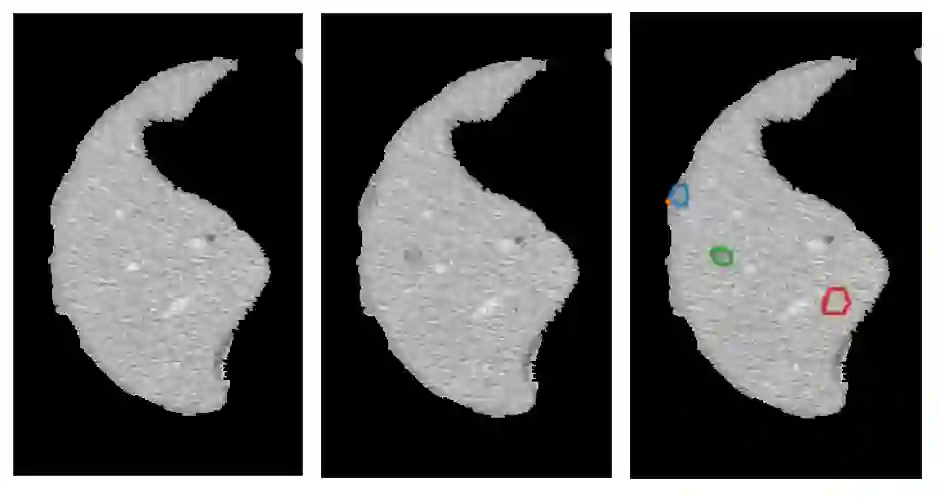

Lesion synthesis received much attention with the rise of efficient generative models for augmenting training data, drawing lesion evolution scenarios, or aiding expert training. The quality and diversity of synthesized data are highly dependent on the annotated data used to train the models, which not rarely struggle to derive very different yet realistic samples from the training ones. That adds an inherent bias to lesion segmentation algorithms and limits synthesizing lesion evolution scenarios efficiently. This paper presents a method for decoupling shape and density for liver lesion synthesis, creating a framework that allows straight-forwardly driving the synthesis. We offer qualitative results that show the synthesis control by modifying shape and density individually, and quantitative results that demonstrate that embedding the density information in the generator model helps to increase lesion segmentation performance compared to using the shape solely.